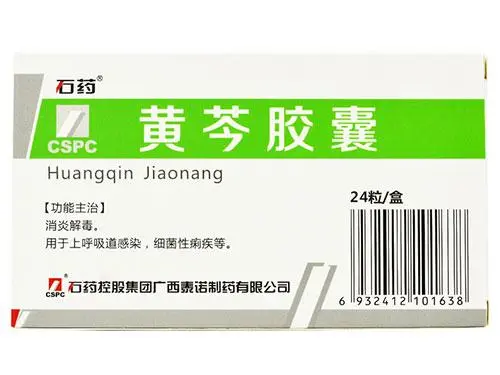

黄芩胶囊的功效与作用,黄芩胶囊具有消炎解毒的功效,用于上呼吸道感染,细菌性痢疾等的治疗,它的药物成分是黄芩,中药黄芩性味苦寒,具有清热燥湿,泻火解毒的功效。

黄芩胶囊是从黄芩中提取的化合物制成的胶囊剂,主要是黄酮类的化合物,具有抗菌抗病毒的功效,黄芩具有广谱的抗菌性,对多种细菌引起的急慢性炎症有抑制作用,黄芩苷还具有明显的解热作用,能够使体温降低。

注意要按照说明书服用,不要过量也不要长期使用,否则容易出现副作用,如果用药三天症状没有缓解,最好到医院就诊,对于脾胃虚寒,少食便溏者要禁止服用。

黄芩胶囊的功效与作用,黄芩胶囊具有消炎解毒的功效,用于上呼吸道感染,细菌性痢疾等的治疗,它的药物成分是黄芩,中药黄芩性味苦寒,具有清热燥湿,泻火解毒的功效。

黄芩胶囊是从黄芩中提取的化合物制成的胶囊剂,主要是黄酮类的化合物,具有抗菌抗病毒的功效,黄芩具有广谱的抗菌性,对多种细菌引起的急慢性炎症有抑制作用,黄芩苷还具有明显的解热作用,能够使体温降低。

注意要按照说明书服用,不要过量也不要长期使用,否则容易出现副作用,如果用药三天症状没有缓解,最好到医院就诊,对于脾胃虚寒,少食便溏者要禁止服用。